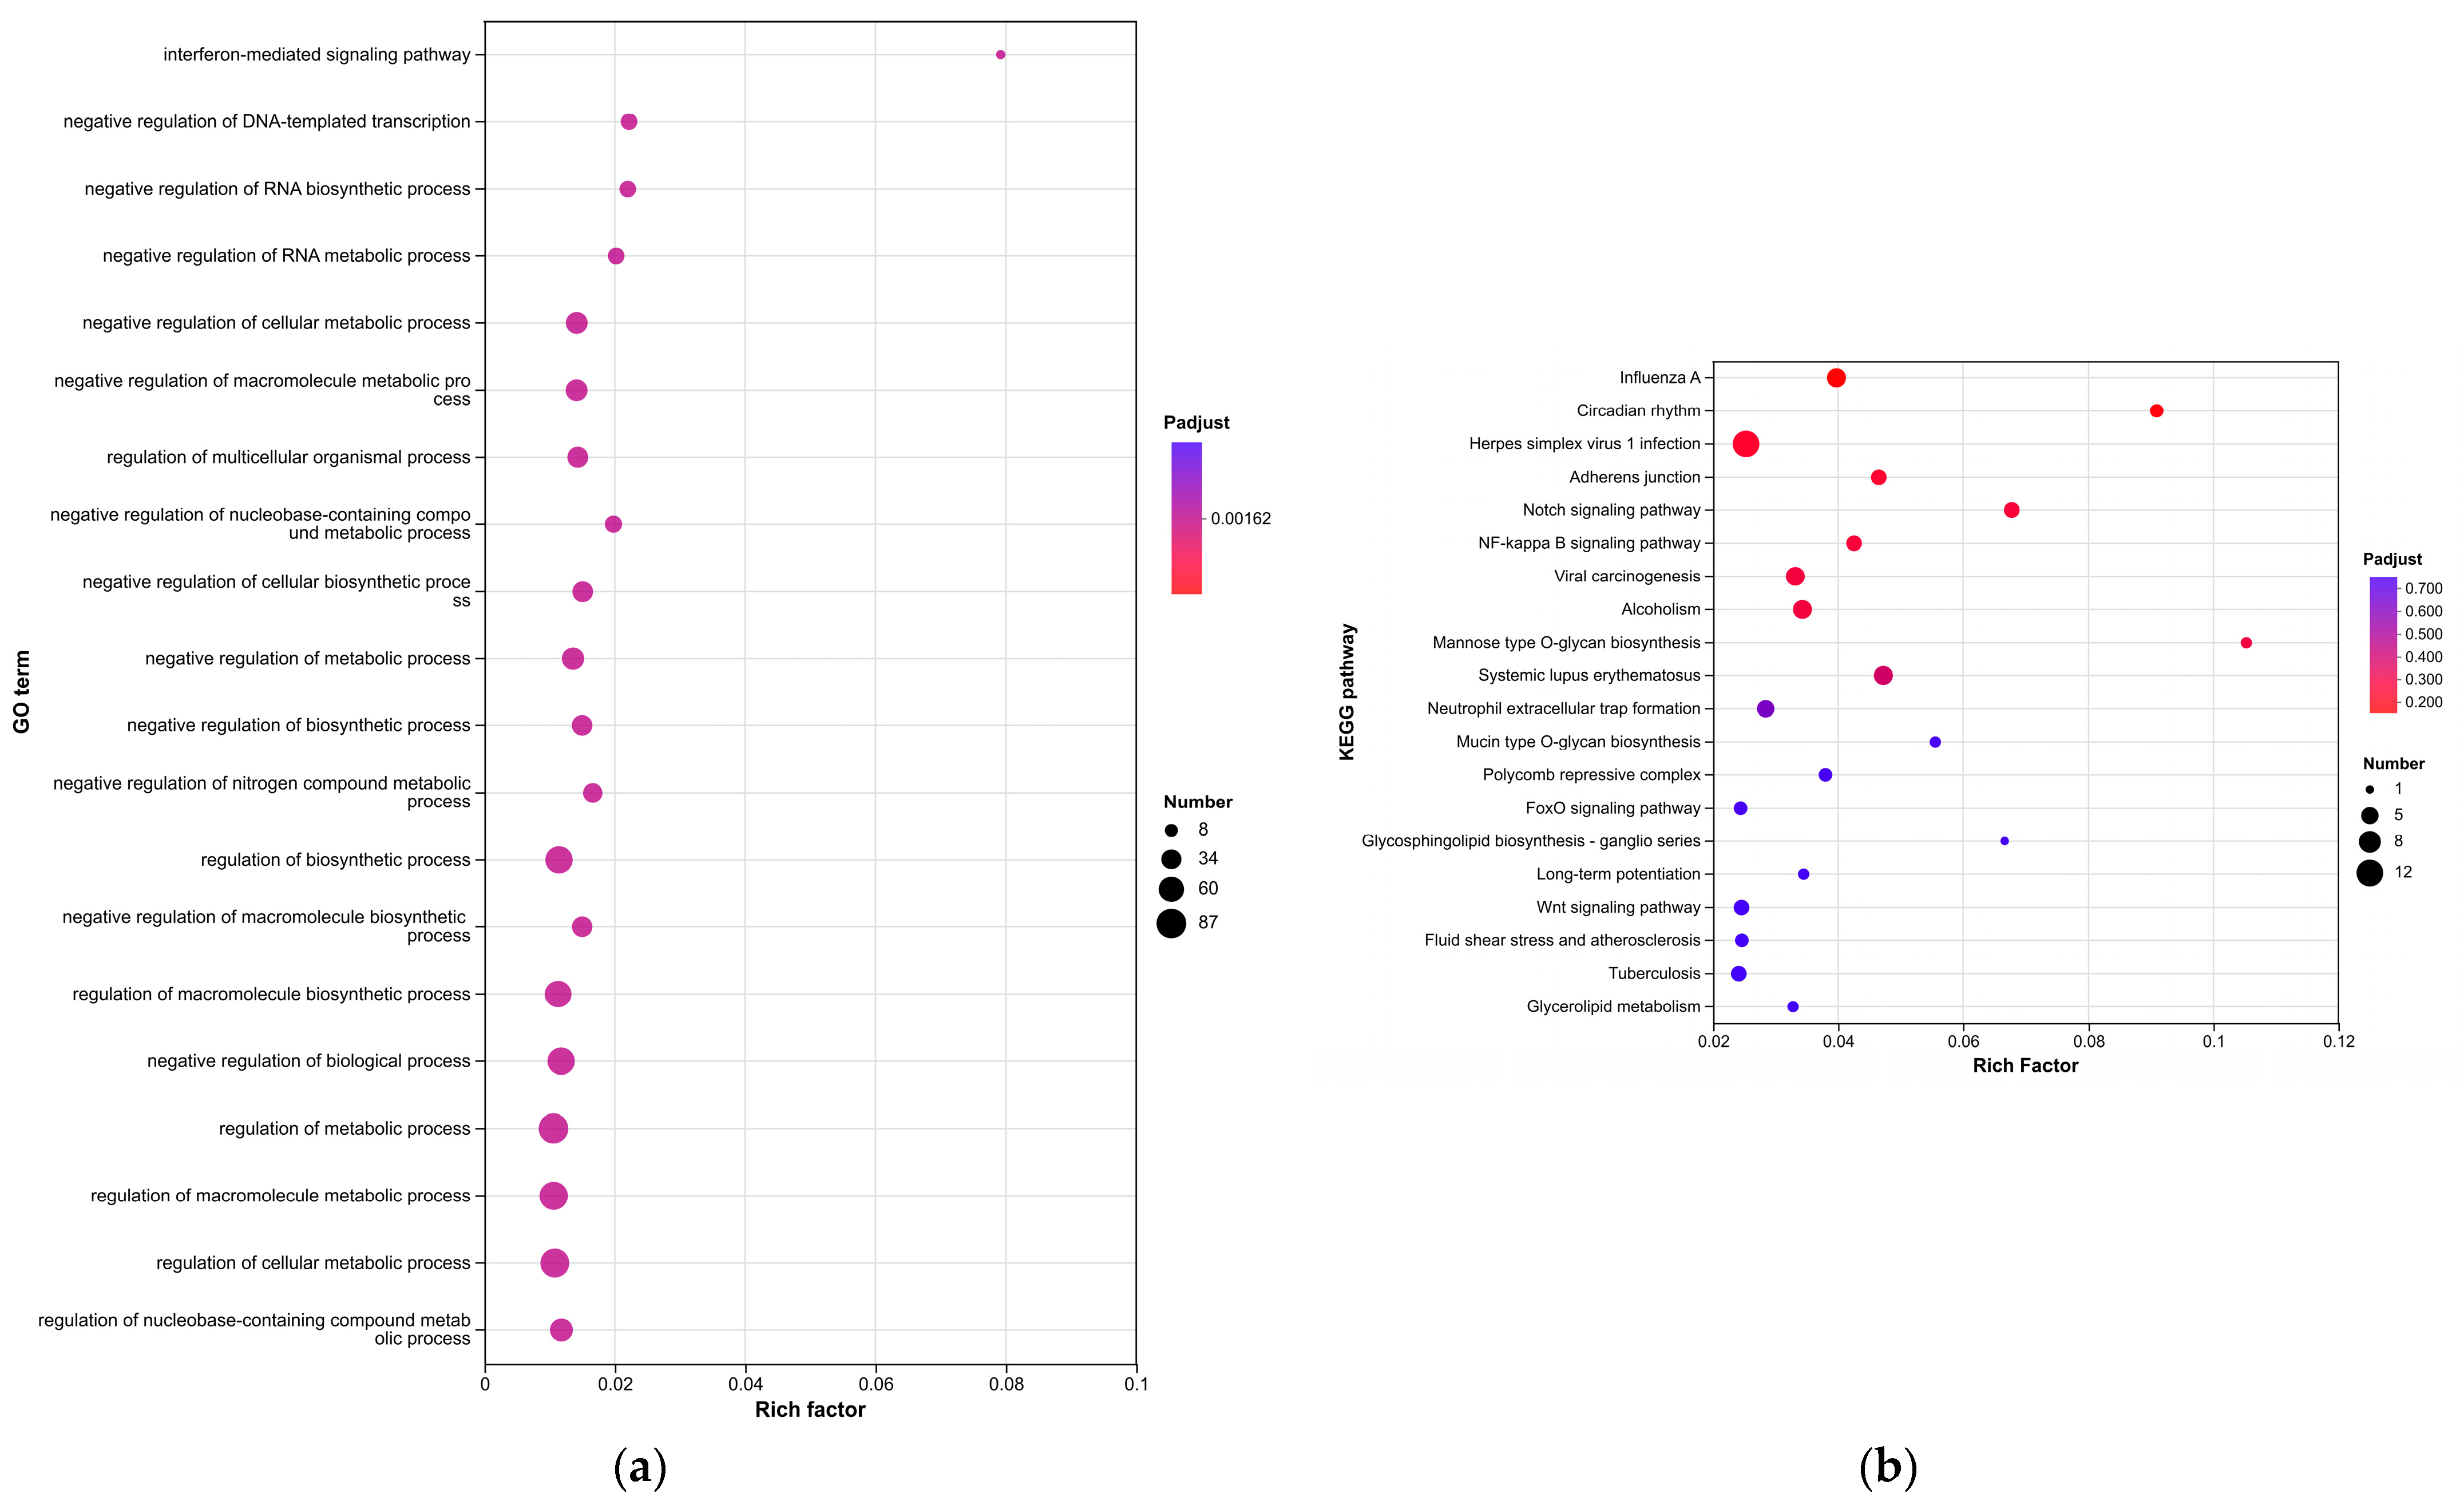

Enrichment analyses, grouped by functional categories (

Table 3), revealed a predominance of RNA processing and immune response pathways consistent with

C. acnes-induced inflammation. These analyses further identified the C-type lectin receptor (CLR) signaling pathway as a key mediator of

C. acnes IA

1–induced inflammation. CLRs, expressed on keratinocytes and immune cells, recognize bacterial glycans, activating NF-κB and MAPK pathways to drive cytokine production [

25]. Our KEGG results, which also enriched NF-κB signaling, suggest a synergistic mechanism where

C. acnes IA

1 exploits CLR-mediated recognition to amplify inflammatory cascades, contributing to the chronicity of acne lesions [

26]. Additionally, enrichment of interferon-mediated signaling and Notch signaling indicates broader immune modulation, with interferons enhancing antiviral-like responses against bacterial PAMPs and Notch regulating epidermal differentiation [

27]. Reactome and Disease Ontology (DO) analyses further linked DEGs to chromatin modification and dermatological conditions, reinforcing acne’s inflammatory nature akin to psoriasis or eczema [

28].